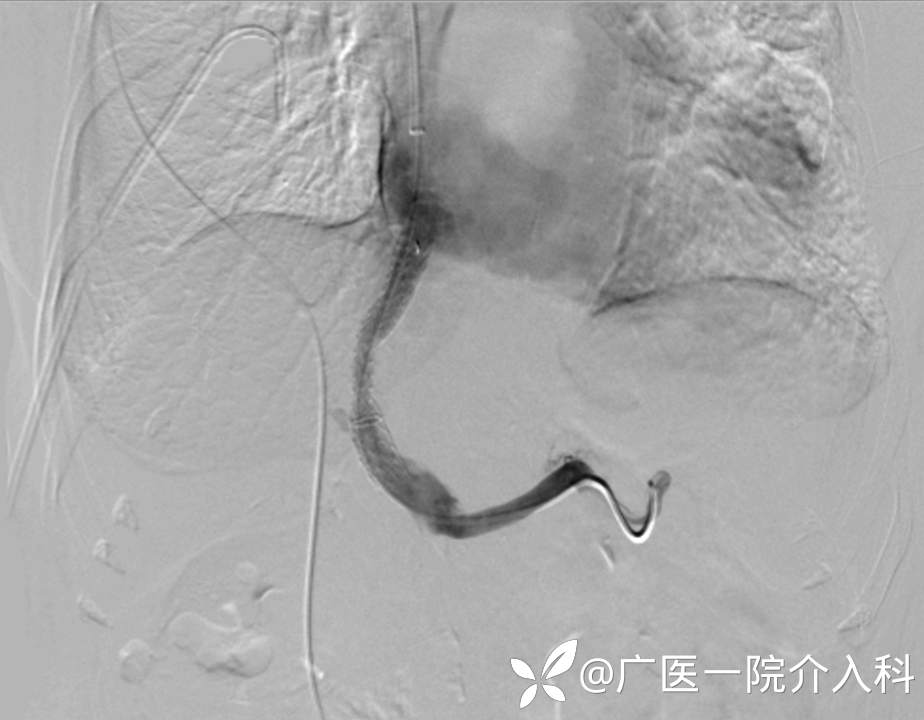

治疗方案:经熊斌教授指导,肝肠外科郭健副主任医师为患者进行经颈动脉内肝门体静脉分流术(TIPS)。

效果:手术顺利完成。术后胸水消失,消化道出血风险降低。

经颈静脉肝内门体支架分流术(TIPS)